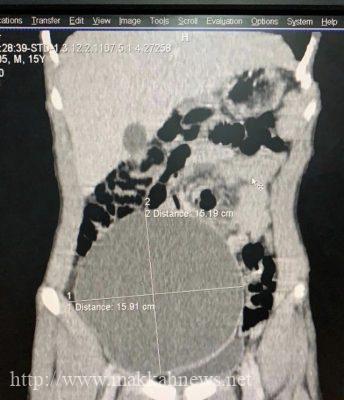

تمكن بفضل الله الفريق الطبي بقسم المسالك البولية وقسم الجراحة العامة بمستشفى عفيف العام من إنهاء معاناة مريض من تورم في الجانب الأيمن من البطن وكذلك تورم في كيس الصفن وبعمل الفحوصات تبين وجود قيلة مائية في خصية معلقة في منطقة الأرب الأيمن وممتدة للحوض والبطن حتى مستوى الفقرة القطنية الثالثة بحجم ٢٦سم ١٦سم ١٣.٥سم وضاغطة على الأمعاء والحالبين مسببة تضخم في الكليتين وقد تم إجراء عملية إستئصال للكيس وتنزيل الخصية لكيس الصفن وإصلاح الفتق الأربي الأيمن بدون أي مضاعفات ولله الحمد واضاف العمري بأن مثل هذا التصفن ضمن 100 حاله عالمياً ومن النادر حدوثها